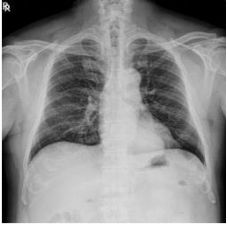

2. A 27-year-old woman had productive cough for one month.